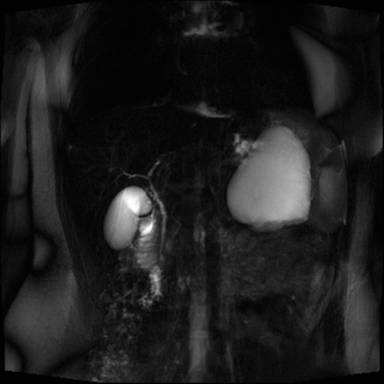

Abdominal US revealed an 8 cm anechogenic mass in the pancreatic tail. Abdominal CT scan was performed using a multi-detector 64 slices CT scanner (Aquilion, Toshiba, Tochigi, Japan) to confirm US findings; unenhanced CT scans showed a well-circumscribed cystic lesion, measuring 8x10 cm in pancreatic tail, with homogeneous low density; an internal this septum was present within the lesions. A contrast-enhanced acquisition was subsequently performed after i.v. bolus (3 mL/sec) injection of 120 mL of a non ionic iodinated contrast agent (Ultravist 370 mgI/mL, Bayer-Shering Pharma, Berlin, Germany) with a scan delay of 120 seconds; an automated dose modulation was used; the cyst wall and the internal septum showed a slight contrast enhancement (Figure 1); the stomach, spleen and left kidney were displaced by the mass. Further diagnostic investigation included a MR scan that was carried out using a 3T MRI (Gyroscan, Philips, Eindhoven, Germany) acquiring axial and coronal T1- and T2-weighted images with and without fat saturation integrated with MRCP T2-weighted hydro-cholangiographic sequences. In particular, the lesion was hyperintense on T2-weighted MR images (Figure 2) and homogeneously hypointense on the pre-contrast T1-weighted MR images showing a mild rim of enhancement after intravenous contrast administration (gadolinium diethylenetriamine pentaacetic-acid) in a volume of 20 mL with 2 mL/s) while maintaining the hypointensity of the central core constant; an internal septum of slight hyperintensity was present within the lesion, that was divided in two parts (Figure 3); MR cholangiopancreatography showed no communication between the lesion and the main pancreatic duct (Figure 4).

Figure 4. MRCP show no communication between cyst and the main pancreatic duct. |

The macroscopic characteristics of true cyst can be well demonstrates on US, CT and MRI images and allow a differential diagnosis with other cystic lesion of the pancreas [19]. In particular, CT and MRI showed in our case a well defined round mass, thin walled with an internal septum that showed a mild rim of enhancement after intravenous contrast administration; both on CT and MRI there was no solid component or central-cyst wall calcification. In this regard, the correct preoperative differential diagnosis based on imaging findings is a crucial point to select the most appropriate treatment, but it remains a very difficult issue; in particular, a true cyst of the pancreas should be differentiated, mainly, from neoplastic or non-neoplastic cysts. From a radiologic point of view an unilocular macrocystic lesion is indicative of pseudocyst in patient with a history of pancreatitis and/or serum amylase increase or for a true pancreatic cyst; conversely, the presence of the internal septum, is suggestive of a neoplastic nature in particular of intra-papillary mucinous neoplasm, when there is communication between the cyst and the main pancreatic duct, or mucinous cystadenoma [19]. In our case, on the basis of the sex and age, as well as the morphological and imaging findings, the hypothesis of mucinous cystadenoma of the pancreatic was made, but, a true pancreatic cyst was histologically demonstrated; however, the evaluation of the content of the cyst by fine needle aspiration was not available since it was not performed.